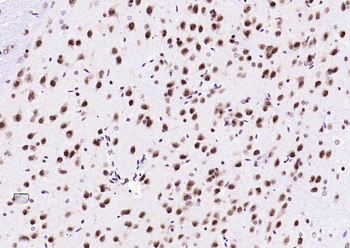

IHC staining of FFPE human brain with Ubiquitin antibody (clone PBQN-1). Required HIER: boil tissue sections in pH9 10mM Tris with 1mM EDTA for 10-20 min followed by cooling at RT for 20 min.